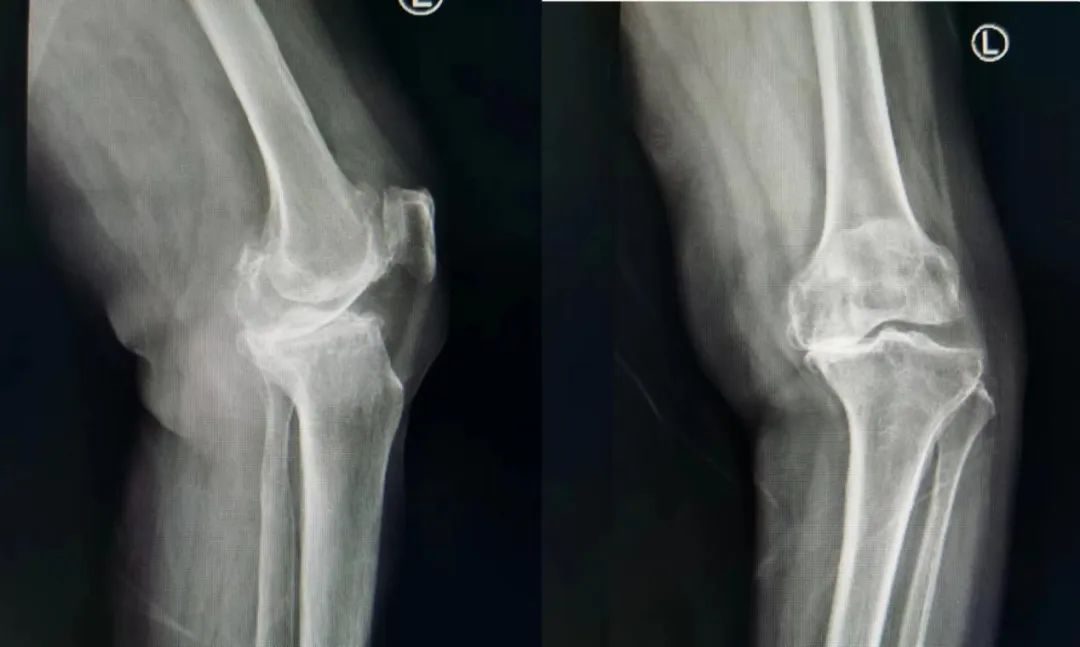

骨关节炎患者应选X线检查,必要时可行CT、MRI及超声等检查进一步明确退变部位、退变程度。骨关节炎受累关节在X线片上的三大典型表现为非对称性关节间隙变窄、关节边缘骨赘形成以及软骨下骨硬化和(或)囊性变。MRI可以观察到骨关节炎关节的软骨厚度变薄、缺损、骨髓水肿、关节积液以及膝关节半月板变性、损伤和腘窝囊肿等,对于临床诊断早期骨关节炎有一定价值。CT的检查一般应用不多,主要是有的关节炎需手术治疗,进行术前评估使用。

目前膝关节置换方面,部分单间室退变的患者,如髌股关节炎、胫股关节单间室骨关节炎,在符合相应的手术指征条件下,也可以选择行相应的单间室人工关节置换手术(如上图),单间室置换能更好的保留患者本体感觉。